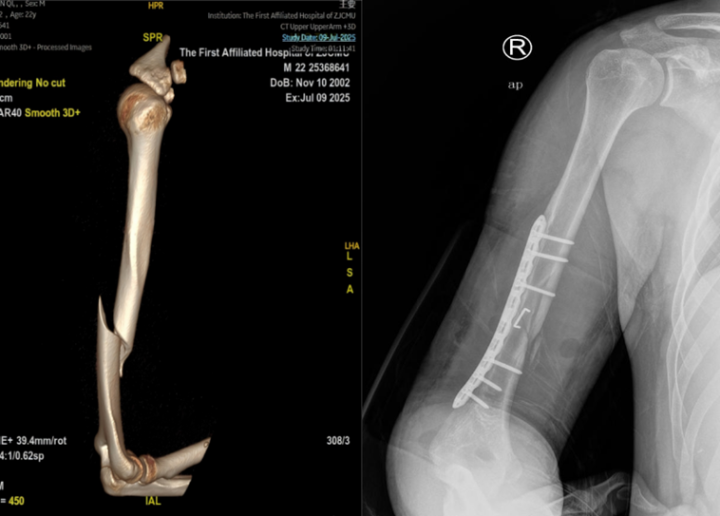

急诊骨伤科医生查体后发现阿琦的腕关节手指背伸困难,诊断结果让所有人倒吸一口凉气:“右肱骨干骨折,合并桡神经损伤!”

经拍X光片检查:肱骨干断裂。

更惊人的是,何先生断掉的肱骨好似麻花一样,呈现螺旋形状。